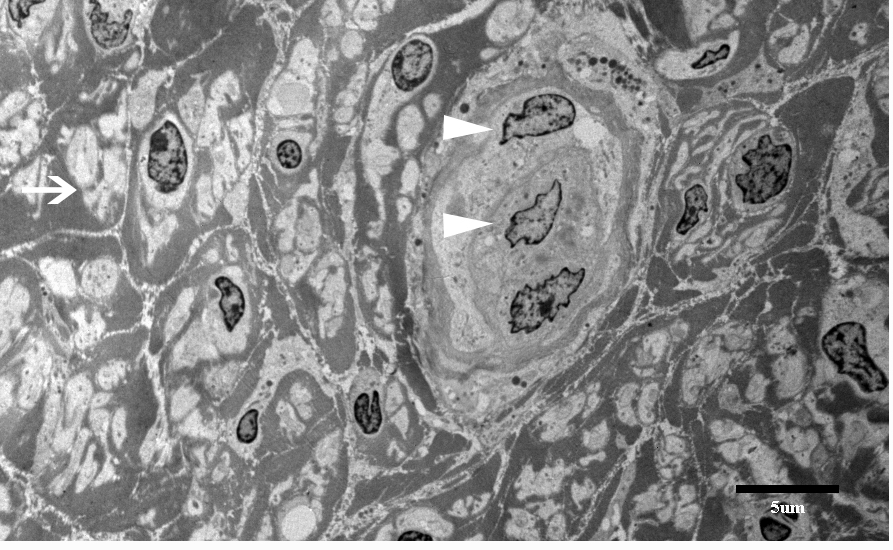

The nerve and muscle specimens from the lower extremity were received and processed per standard muscle and nerve workup protocols including enzyme histochemistry, special stains for nerve and muscle, nerve teasing, and electron microscopy. H&E stained sections of the nerve biopsy show cross sections of sural nerve and surrounding connective tissues (Figure 1A). Blood vessels show no evidence of vasculitis, and Congo red stain displays no evidence of amyloidosis. There is significant fibrosis of the peri-, epi -or endoneurium observed. These are best highlighted with trichrome stain (Figure 1D). Trichrome also shows no large myelinated fibers. A neurofilament immunostain displays evenly distributed and moderately diminished complement of axons (Figure 1B). One micron thick, toluidine blue stained sections display cross sections of several nerve fascicles. This stain shows a complete absence of thickly myelinated fibers (Figure 1C). No supernumerary Schwann cell accumulations are seen. Endoneurial vessels have enlarged endothelial cells. Ultrastructural analysis of these sections confirms the observations seen on thick sections (Figure 2). There is no discernible thick or thin myelin present around axons. Unmyelinated fibers have loosely arranged membranes around them, and Schwann cell nuclei are present. No supernumerary Schwann cells are present (Figure 2). The tease preparation displays strands of fibrous tissue without any discernable myelinated fibers.